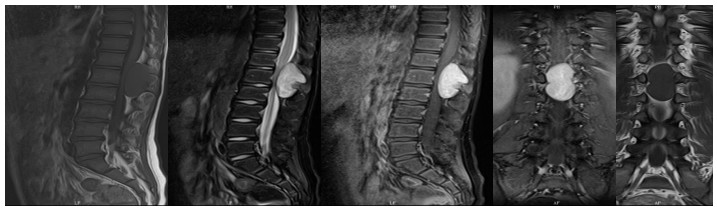

59歲鄒阿姨術(shù)前胸椎MRI檢查